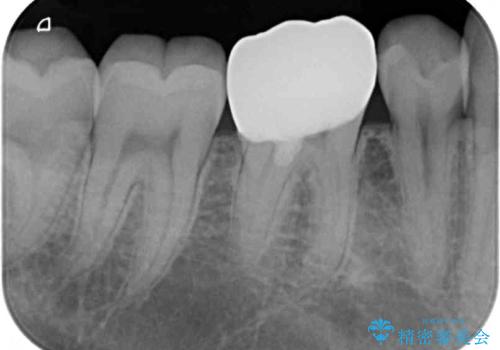

虫歯除去後に痛みは収まり、神経も保存することができました。

変色していた歯もセラミッククラウンで自然な色合いとなり、患者様には大変満足していただきました。